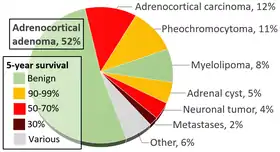

The most common location for neuroblastoma to originate (i.e., the primary tumor) is in the adrenal glands. This occurs in 40% of localized tumors and in 60% of cases of widespread disease. Neuroblastoma can also develop anywhere along the sympathetic nervous system chain from the neck to the pelvis. Frequencies in different locations include: neck (1%), chest (19%), abdomen (30% nonadrenal), or pelvis (1%). In rare cases, no primary tumor can be discerned.[9]

- ↑ Data and references for pie chart are located at file description page in Wikimedia Commons.